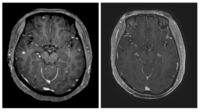

[아이건강톡] 산만한 아이 ‘ADHD’일까

아들딸 구별 말고 하나만 낳아 잘 기르자던 시대는 이미 지났고 하나뿐인 아이가 누구보다 잘 자랐으면 하는 기대와 관심이 훨씬 더 큽니다. 특히 최근에는 아이들의 ‘마음 건강’에 대한 관심이 늘어나면서 소아청소년정신과의 문턱이 낮아지는 등 긍정적 변화도 생겼습니다.때론